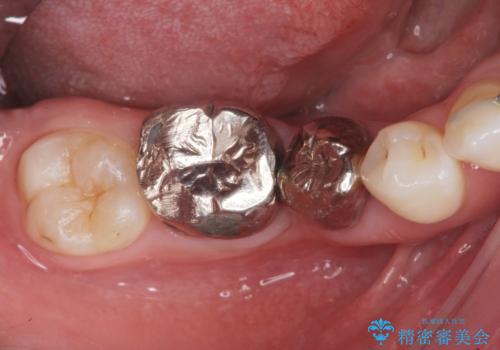

銀歯を白くしたい セラミック治療

- 見栄えが悪く、歯ブラシのしづらい銀歯を白くしたい、とセラミック治療を希望され来院されました。

- 26.4万円(ジルコニアクラウン×2・仮歯×2)費用は治療当時の料金となります